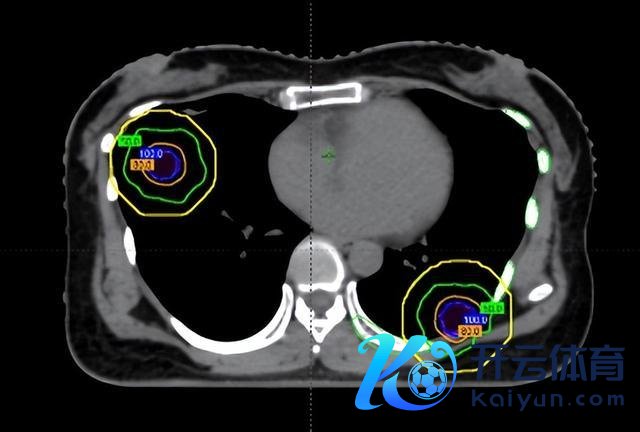

在调停前,团队通过四维CT对三个病灶进行精确定位,尤其是紧贴肋骨的阿谁病灶,连与肋骨之间极其微小的裂缝齐被明晰标注出来。

随后参加最中枢的剂量筹算步伐。胡英教训与李忠伟、雷大明物理师反复推演射澄莹径和强度溜达,把高剂量区域严格法例在肿瘤规模内,同期让剂量在极短距离内速即着落。不错解析为,在体内完成了一次“毫米级雕琢”:肿瘤被精确障翳,而近在目前的肋骨却被保护在安全规模内。